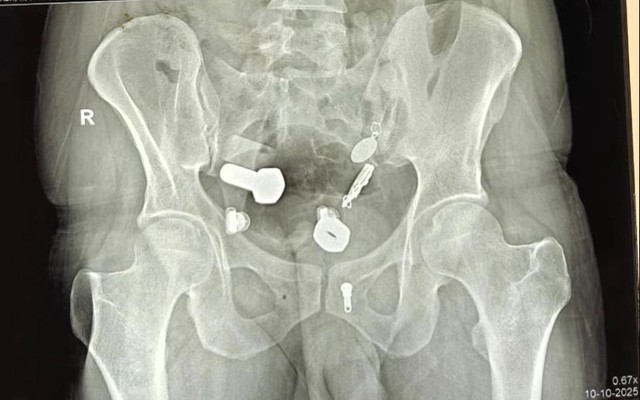

Các bác sĩ đã bị sốc khi kết quả chụp chiếu cho thấy một chiếc đồng hồ mắc kẹt trong thực quản của bệnh nhân, cùng với các mảnh sắt, đai ốc và bu lông mắc kẹt trong ruột già, theo như Need To Know đưa tin .

Hình ảnh chụp X-quang cho thấy khối vật thể kim loại kỳ lạ bên trong dạ dày của người đàn ông.